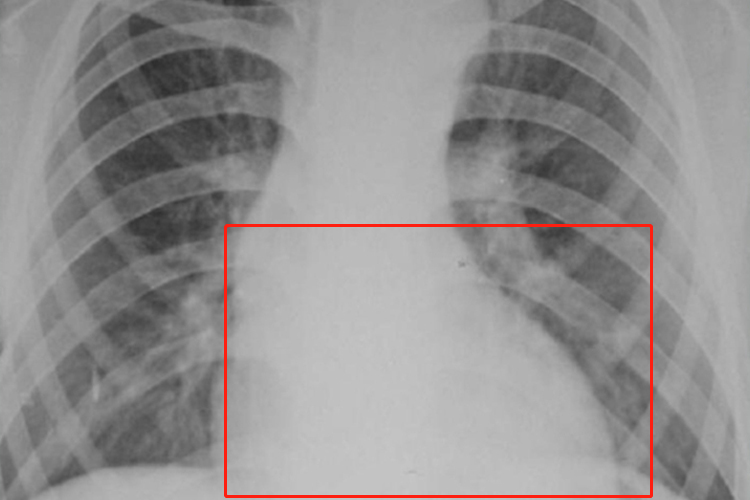

约80%的患者伴有先天性心血管畸形,常见主动脉进行性扩张、主动脉瓣关闭不全等情况,X线检查可见左心室增大,心脏呈靴形。